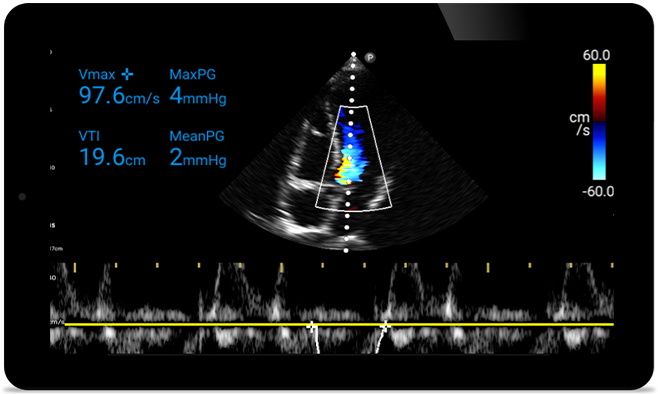

Act faster to protect their heart

When seconds count, portable ultrasound can make the difference. Lumify can provide the high-definition imagery you need whenever and wherever you need it.

Opportunity to potentially reverse cardiomyopathy